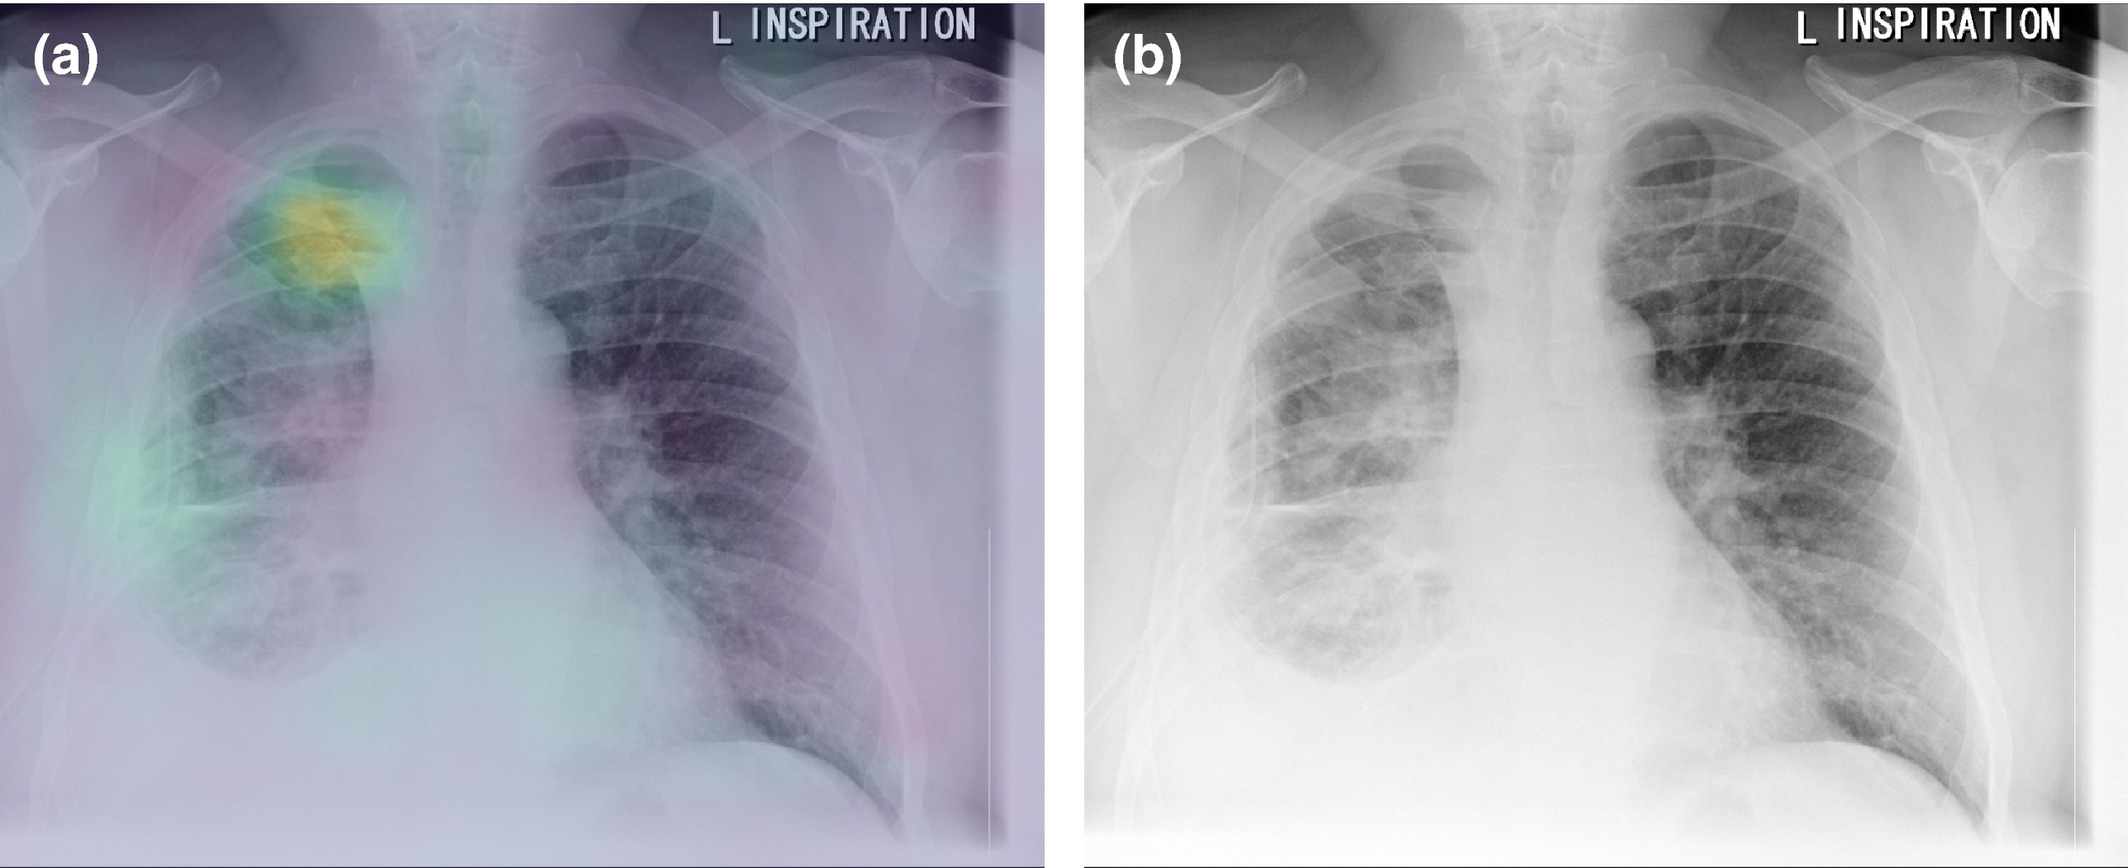

Evidence demonstrating model accuracy and clinician performance improvement must be robust as the mechanisms of a trained algorithm’s decision-making processes are often opaque.39 In CXR interpretation, where some findings may be subjective, model opacity may lead to over- or under-confidence in generated results. This may reduce support for system implementation and degrade clinician adoption.40 Research on improving algorithm interpretability is generating useful potential solutions.41, 42 Interrogating black box models to assess the reasons for their conclusions can be useful in minimising internal system bias. One method for assessing the areas in an image given most attention by a machine learning model is to visualise a heat map overlaid onto image pixels. This graphs the attention given to each region of the image over the multiple layers of the model network (Fig. 1). However, heatmaps are often difficult to interpret and may be misleading.43

Fig. 1 (a) Heatmap investigating an exemplar algorithm25 in classifying pneumothorax, demonstrating its focus on the right apical pneumothorax rather than the right-sided intercostal drain. (b) Original image demonstrating right apical pneumothorax.